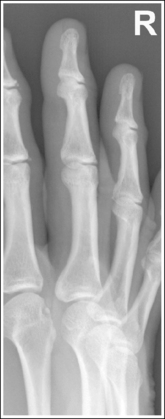

Finger: Posteroanterior Projection

See Figure 4-1 and Box 4-2.

The finger demonstrates a PA projection. The soft tissue width and midpoint concavity are the same on both sides of the phalanges.

• Finger rotation is controlled by the amount of palm pronation. A PA projection is accomplished when the palm is positioned flat against the IR (Figure 4-2).

• Detecting finger rotation. Because the thumb prevents the hand from rotating laterally, medial rotation is the most common rotation error. Take a few minutes to study a finger skeleton, and note how the midpoints of the phalanges have equal side concavity when it is placed in a PA projection. Also, note that the anterior surface is concave, whereas the posterior surface is slightly convex. As the skeleton is rotated internally or externally, the amount of concavity increases on the side toward which the anterior surface is rotated, whereas the side toward which the posterior surface rotates demonstrates less concavity. The same observations can be made about the soft tissue that surrounds the phalanges. More soft tissue thickness is present on the anterior (palmar) hand surface than on the posterior surface, so the side demonstrating the greatest soft tissue width on an image is the side toward which the anterior surface was rotated. Look for this midpoint concavity and soft tissue width variation to indicate rotation on a PA finger projection (see Image 1). Note on a hand skeleton that the second metacarpal is the longest of the finger digits and that the length decreases with each adjacent metacarpal. This information can be used to determine whether the patient's finger was internally or externally rotated for a mispositioned PA finger image. If the finger was externally rotated, the aspect of the phalanges demonstrating the greater midpoint concavity faces the thumb or longer metacarpal (see Image 1). If the finger was internally rotated, the aspect of the phalanges demonstrating the greater midpoint concavity faces the shorter metacarpal.

Image 1

No soft tissue overlap from adjacent digits is present.

• Spreading the fingers slightly prevents soft tissue overlapping from adjacent fingers. It is difficult to evaluate the soft tissue of an affected finger when superimposition of other soft tissue is present.

The interphalangeal (IP) and metacarpophalangeal (MP) joints are demonstrated as open spaces, and the phalanges are not foreshortened.

• Open IP and MP joint spaces and unforeshortened phalanges are demonstrated when the finger is fully extended and the central ray is perpendicular and centered to the proximal IP (PIP) joint. This finger positioning and central ray placement align the joint spaces parallel with the central ray and perpendicular to the IR, as shown in Figure 4-3, resulting in open joint spaces. It also prevents foreshortening of the phalanges, because their long axes are aligned parallel with the IR and perpendicular to the central ray. The alignment of the central ray and IR with the joint spaces and phalanges changes when the finger is flexed. In Figure 4-4, note how finger flexion causes the phalanges to foreshorten and be superimposed on the joint spaces (see Image 2).

The soft tissue width and the concavity of the phalangeal midshafts on either side of the phalanx are not equal; the finger was rotated for the image. Because the side of the phalanges with the greater concavity and soft tissue width is facing the thumb, the finger was rotated externally for the image.

Place the finger in a PA projection by rotating the finger slightly internally. The hand should be flat against the IR.

The IP and MP joints are closed, and the distal and middle phalanges are foreshortened; the patient's finger was flexed.

Extend the patient's finger, and place the palm flat against the IR. If the patient is unable to extend the finger, image it in an AP projection, elevating the proximal metacarpals until the affected phalanx is parallel with the IR or the affected joint space is perpendicular to the IR (see Figure 4-5).